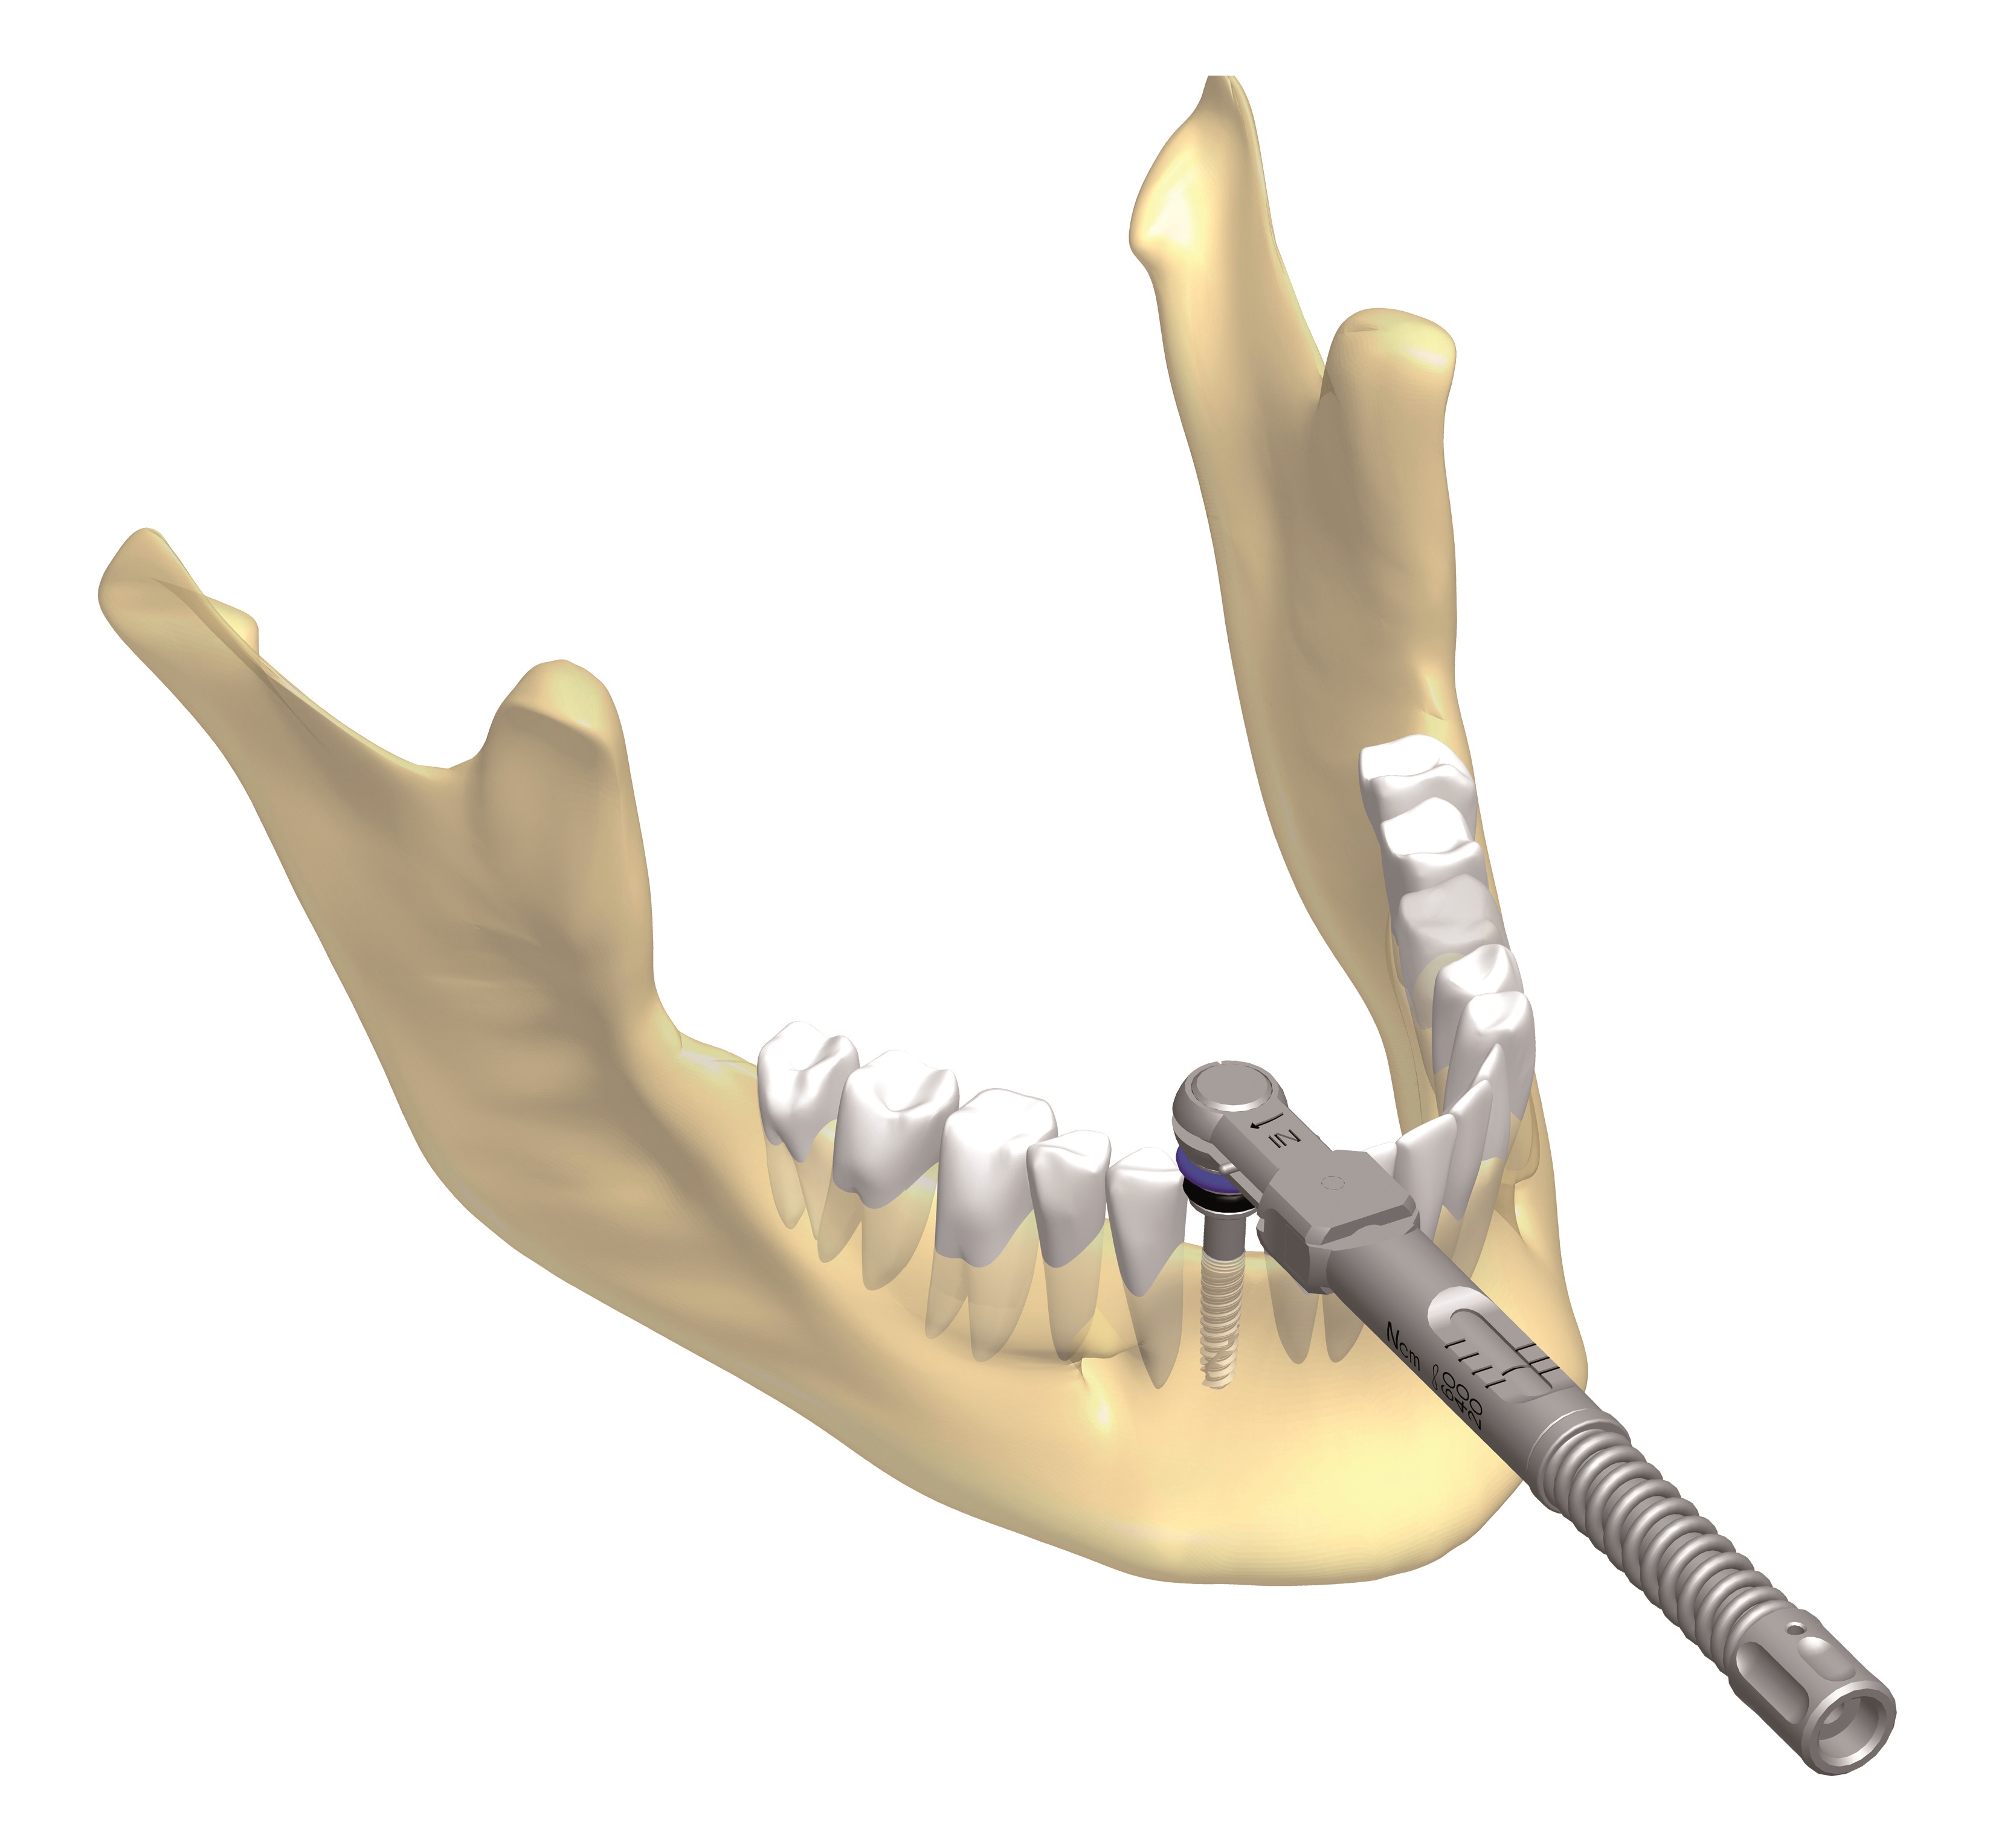

3. A következő lépés a megfelelő méretű implantátum kézi és gépi eszközökkel történő behelyezése.